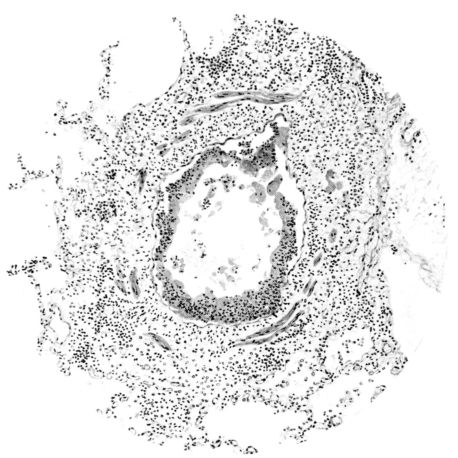

FIG. IV. AUTOPSY NO. 205. CONGESTION AND EDEMA OF THE SUBMUCOSA AND REGENERATION OF THE TRACHEAL EPITHELIUM.